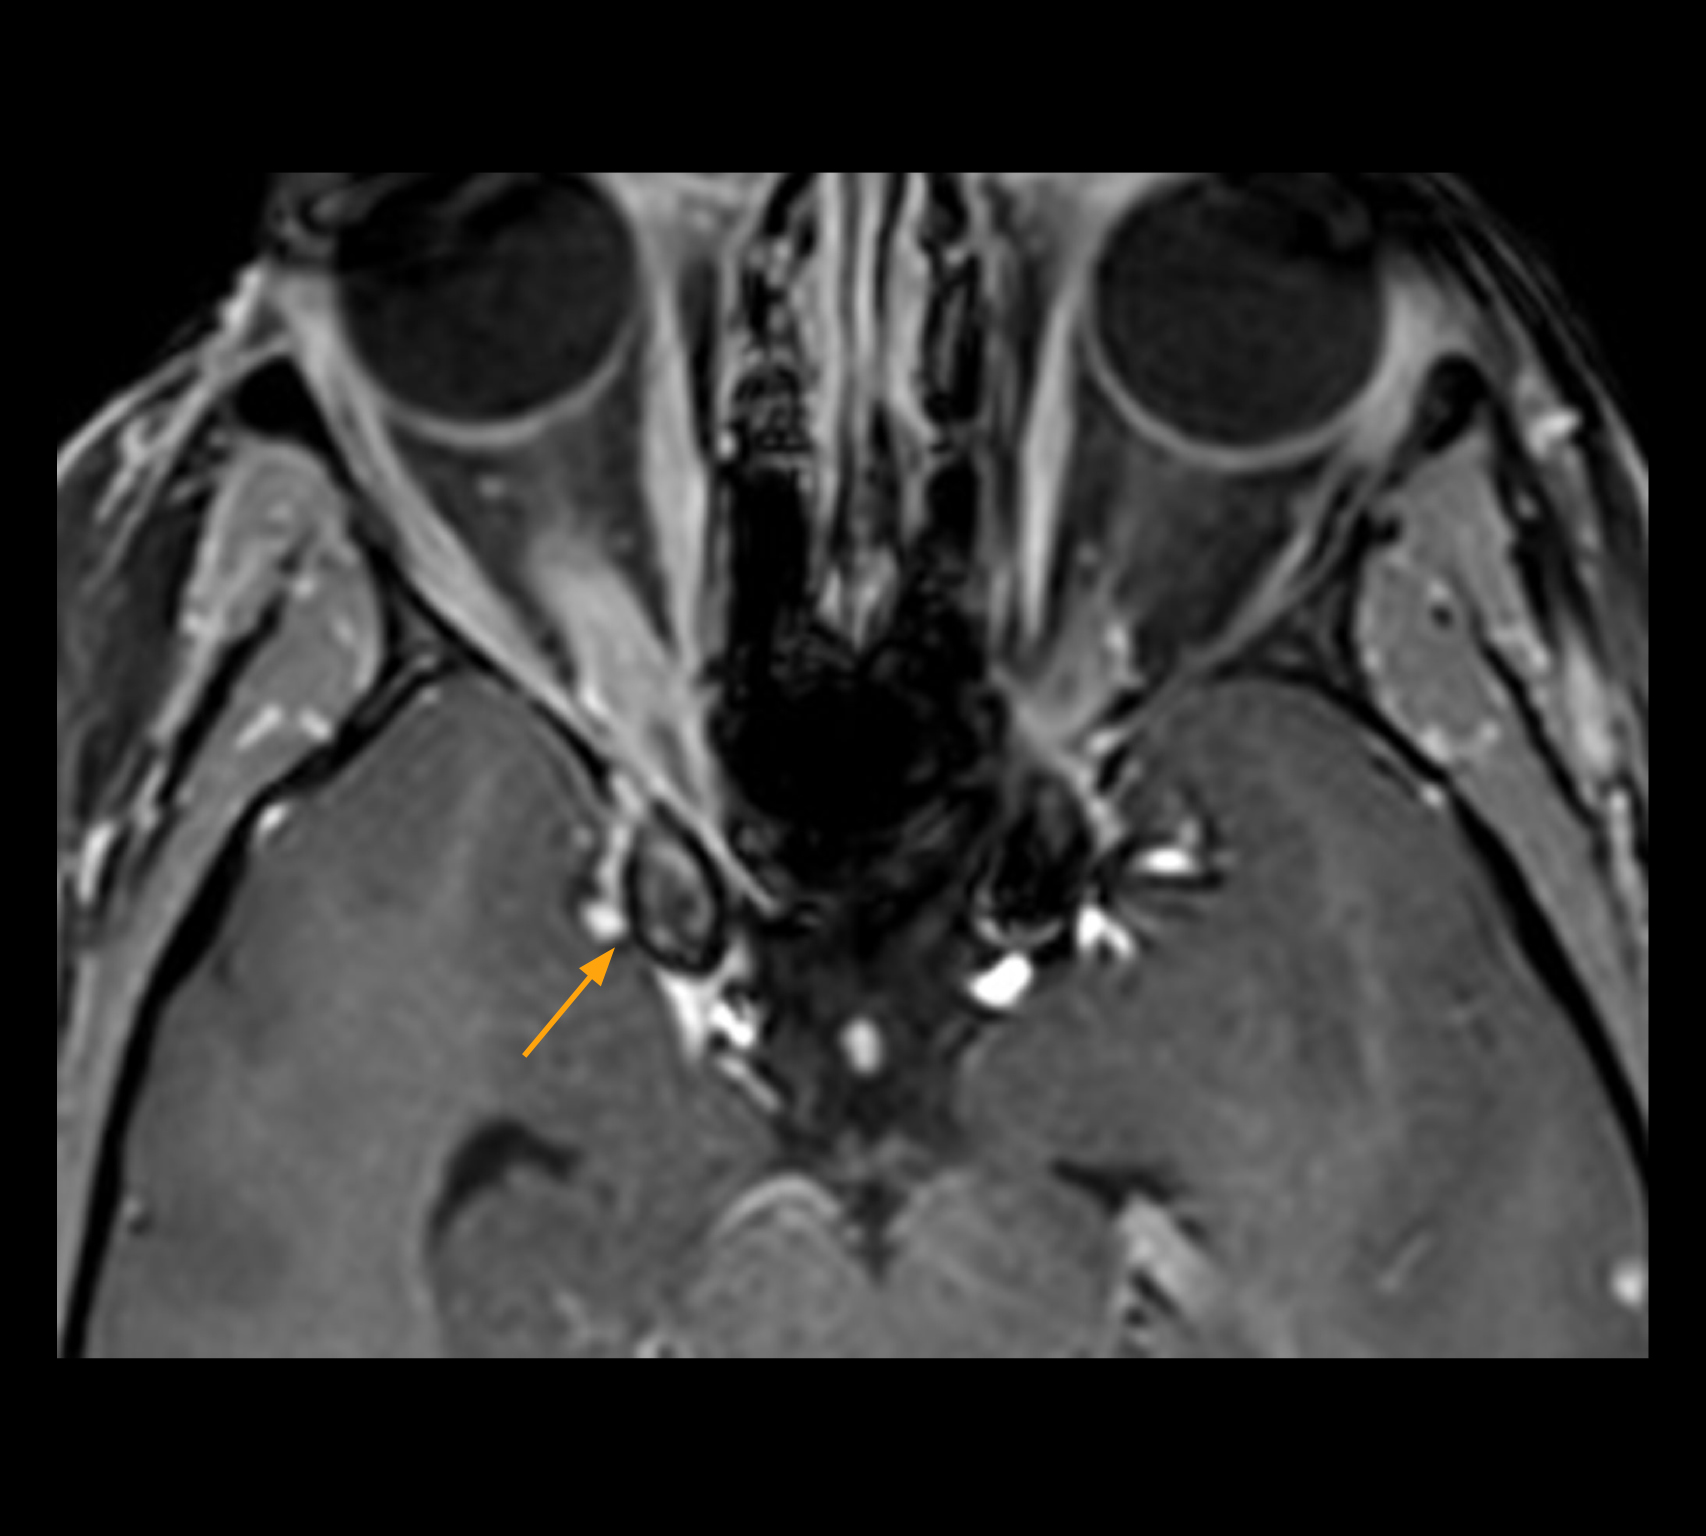

Imaging of the optic nerve sheath

High-resolution MRI impressively demonstrates the compression and narrowing of the right optic nerve in this case of optic nerve sheath meningioma (ONSM). The coronal T2-weighted images show the hyper-intense, half-moon shaped lesion, that is clearly visible in the axial T1W image after contrast injection (right). These imaging findings were so convincing that there sponsible neurosurgeon did not consider a pretherapeutic histological clarification.

Imaging of the optic nerve sheath

High resolution-MRI impressively demonstrates the compression and narrowing of the right optic nerve in this case of optic nerve sheath meningioma (ONSM). The coronal T2-weighted images show the hyper-intense, half-moon shaped lesion, that is clearly visible in the axial T1W image after contrast injection (right). These imaging findings were so convincing that there sponsible neurosurgeon did not consider a pretherapeutic histological clarification.